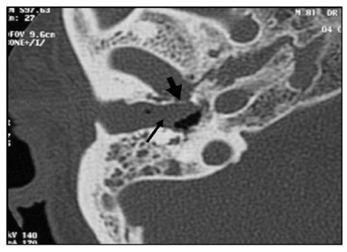

Figure 1 Axial scanner (TDM) in a patient aged diabetes, refereen reason for the paralysis of the facial nerve that has grown despite the oral treatment. The scanner shows the right temporal bone destruction. Note the disappearance of the posterior wall of the external ear canal (short arrow). Mastoid air cells are secondarily involved and clouded (long arrow) from the left side well ventilated.

The MEO is an otological infection that has life-threatening complications. It is considered as a complication of external otitis.2 Occurs mainly in the elderly who have diabetes or another condition that compromises the immune system. Doctors must be able to recognize this infection, initiate treatment, and refer patients to an Otolaryngologist. The precise etiology of this condition is unknown, but theories related to impaired immunity, the local tissue microangiopathie and even modified biochemistry of earwax have been proposed. Infection of the soft tissues of the external ear canal is common, especially in hot and humid climates. The usual triggers are trauma (often caused by q-tips) and exposure to the pool of water. The most frequently found germ is Pseudomonas aeruginosa, is not a normal germ of the EEC.3 Other possible germs include Staphylococcus epidermidis,4 gram negative bacteria and fungi. External otitis patients complain of earache and sensitivity to atrial movement. The otorrhoea may be present, the obliteration of the external ear canal by edema and secretions can cause hearing loss, or a feeling of fullness in the ear. The disease comes from the EEC and propagates through the osteo-cartilaginous junction to involve soft tissue under the temporal bone. Granulation tissue is usually present in the EEC. The spread of the infection can cause thrombosis of the lateral sinuses and petrous sinus upper and lower. Initially, the progressive skull base osteomyelitis can cause cranial Polyneuropathy, paralysis of the facial nerve being the most common; cranial nerves IX, X, and XI (the jugular foramen syndrome) nerves and cranial nerve XII (hypoglosse channel) are less often involved with the development of the sphenoidal sinusitis. Imaging to show the extension of the infection to the bony structures is usually required to establish the diagnosis of MEO6 imaging modalities include tomographic (CT) scan, scan bone to the technetium Tc99m medronate methylene diphosphonate, and scintigraphy to Ga 67 gallium citrate. CT is used to determine the location and extent of diseased tissue (Figure 1 & Figure 2). The temporal bone is the first os to be affected, with an imminent involvement of petrous apex and the mastoid process. Extratemporal extension has become rare since the introduction of powerful antibiotics. In evaluating the scanner, it is important to remember that at least one third of the minerals is lost before the radiological changes are becoming apparent; Conversely, the bone remineralization continued long after that infection is Gueriela scan is a diagnostic sensiblemais non-specific to the MEO, if to the 67Ga scintigraphy is available, (Figure 3). It must be used for the initial diagnosis and follow-up tool.7 Using in combination imaging modalities, it is possible to prove that the temporal bone is reached (scan and bone scan to the 99mTc) with infectious process (Ga 67 scintigraphy).6 MRI is of interest in advanced forms allowing a better analysis of the deep spaces of the face, the nervous foramina, merien hard spaces and the Medullary bone in the base of the skull.